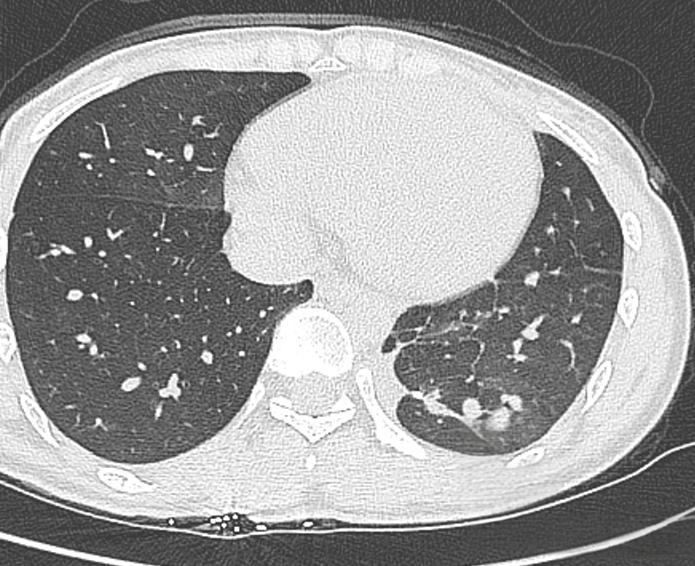

ct肺纹理增多

双肺纹理增多 影像显示肺部血管和支气管纹理较正常更为密集,可能与